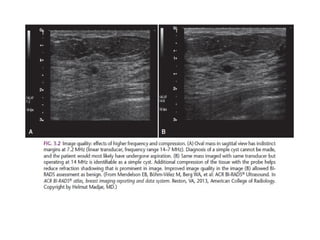

The margin of a lesion can be:

Obscured or partially obscured, when the margin is hidden by superimposed

fibroglandular tissue. Ultrasound can be helpful to define the margin better.